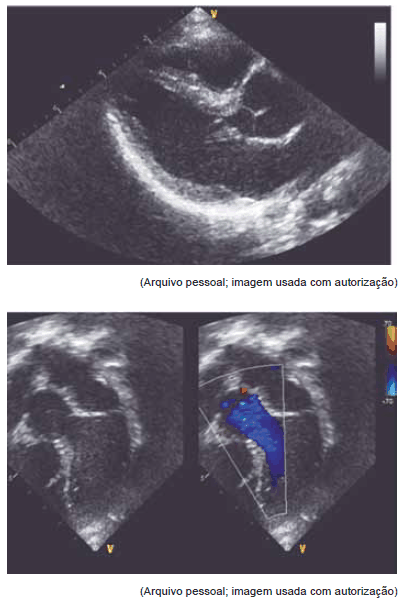

Estas imagens de ecocardiograma dizem respeito a paciente com síndrome